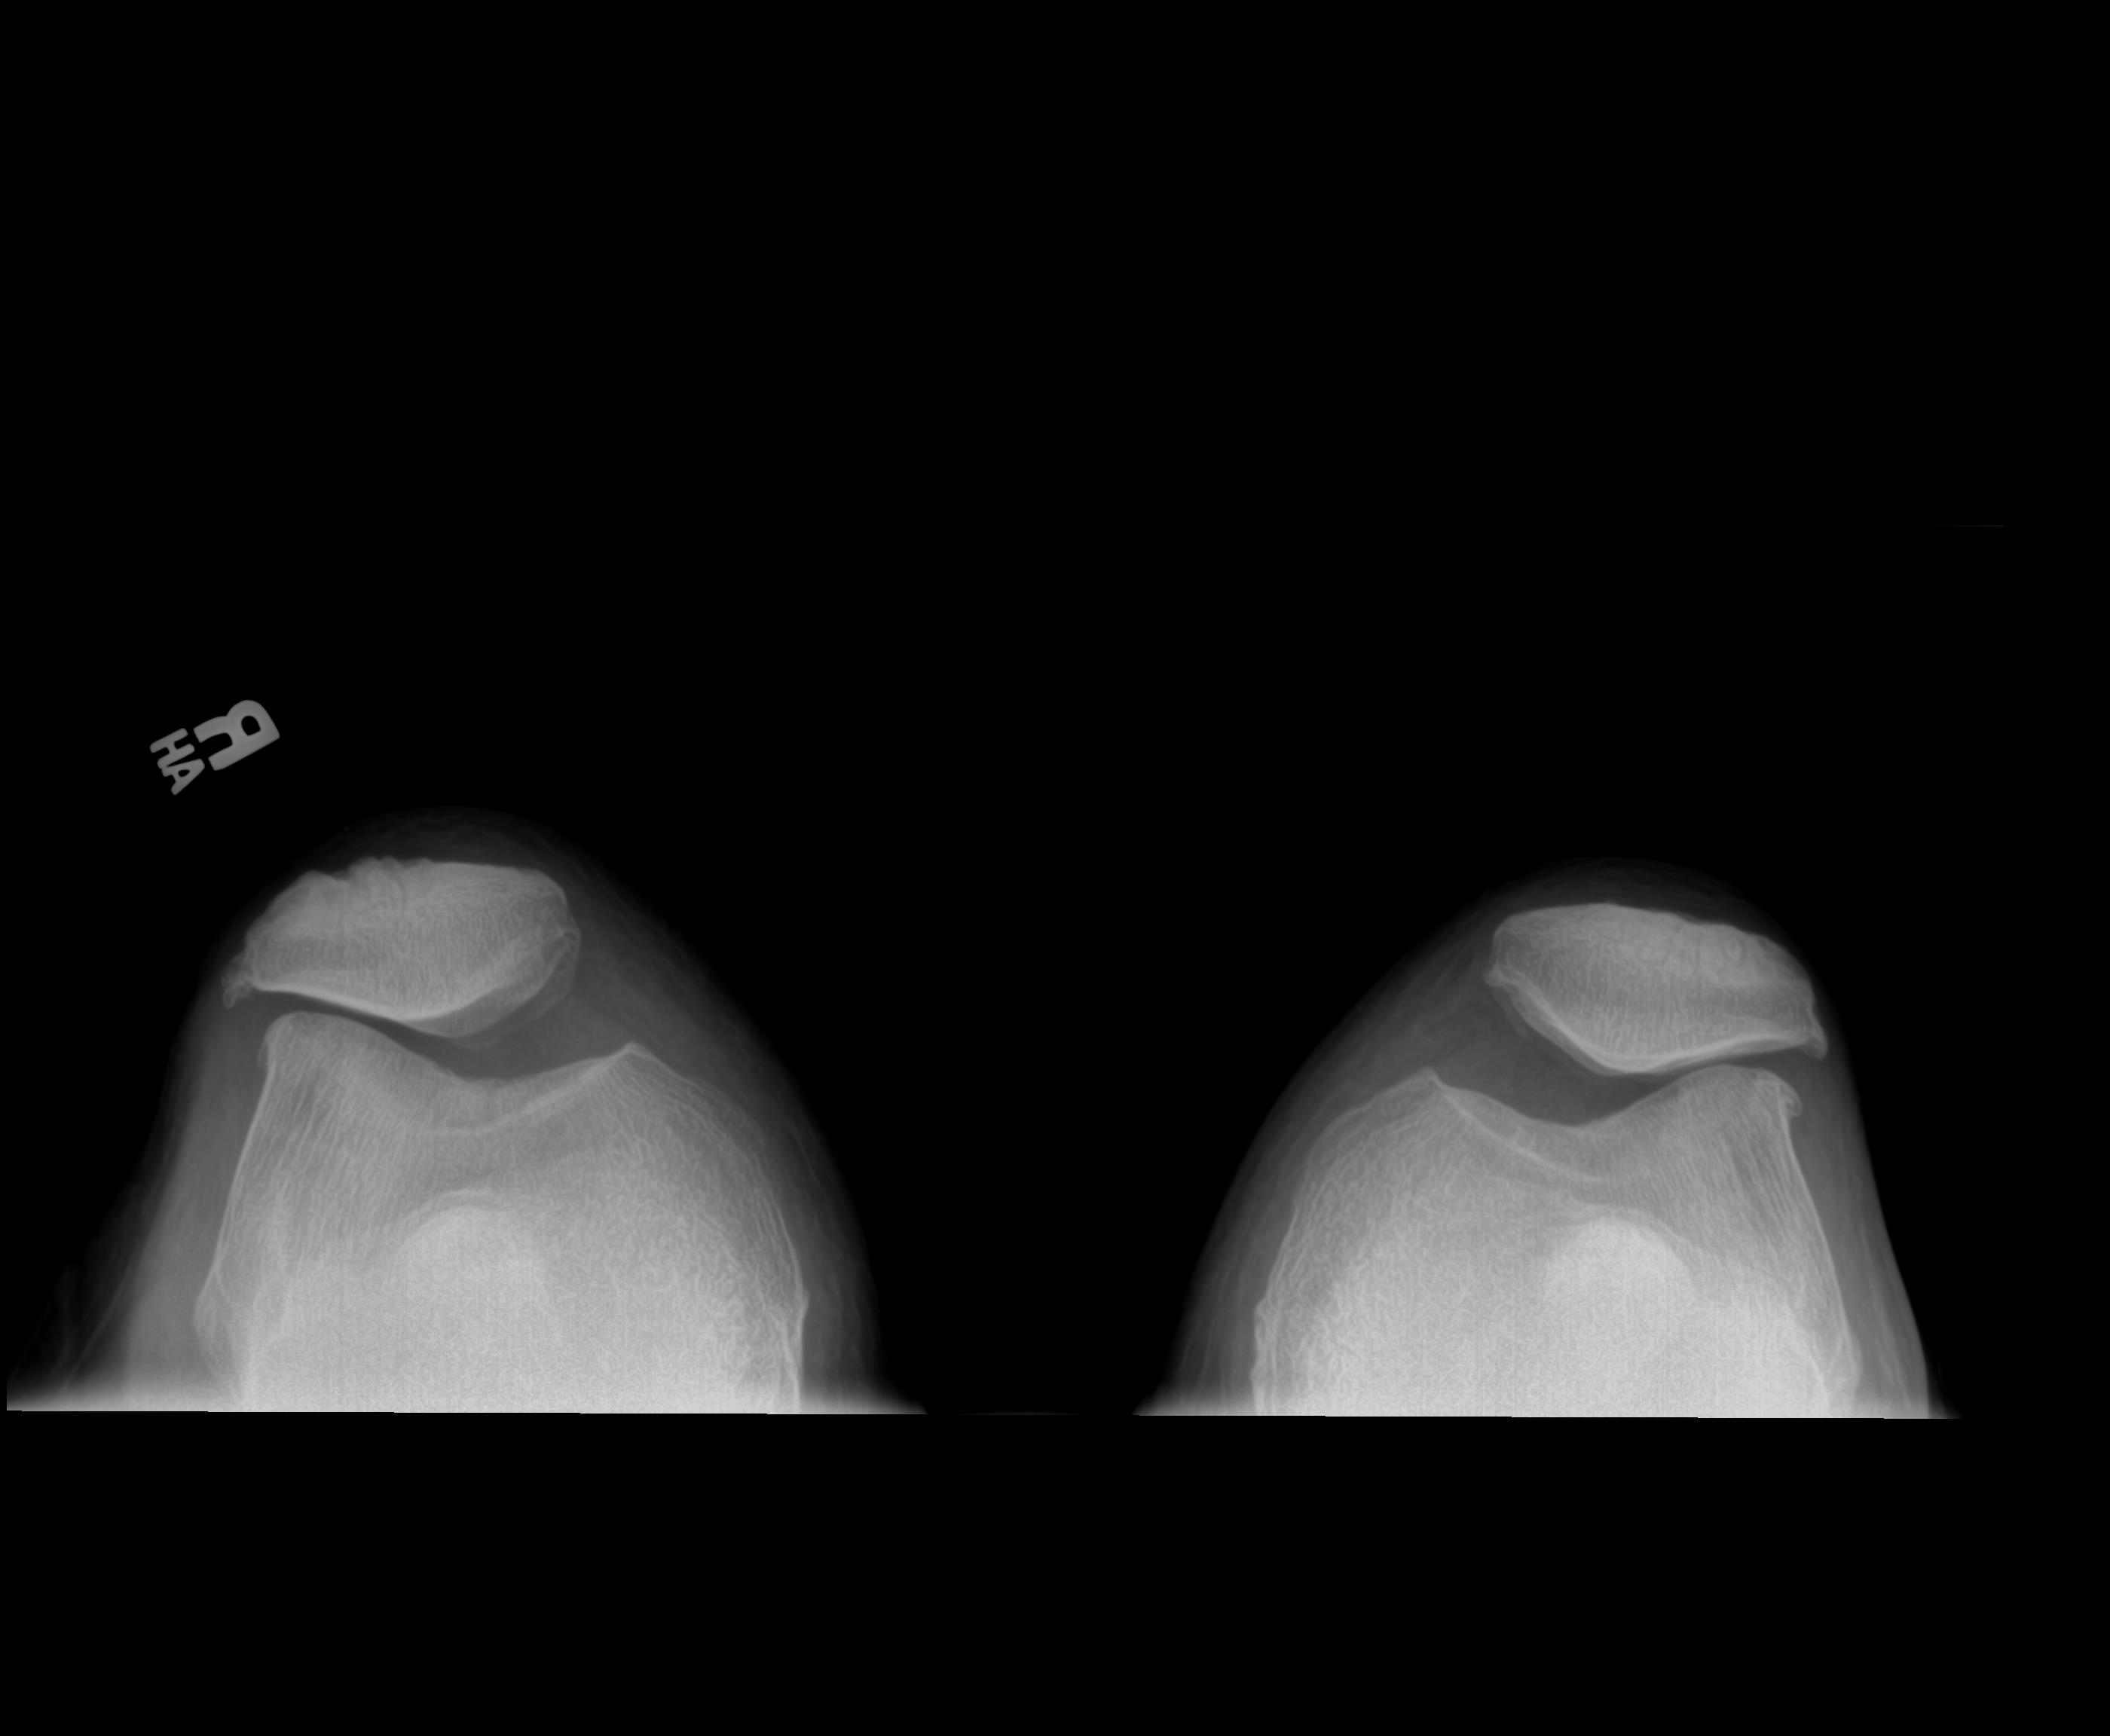

Before – Both Knees

Before – knee caps